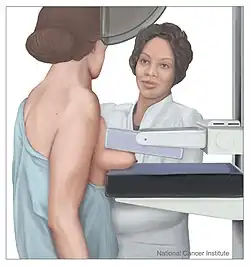

Breast cancer screening refers to testing otherwise-healthy women for breast cancer in an attempt to diagnose breast tumors early when treatments are more successful. The most common screening test for breast cancer is low-dose X-ray imaging of the breast, called mammography.[28] Each breast is pressed between two plates and imaged. Tumors can appear unusually dense within the breast, distort the shape of surrounding tissue, or cause small dense flecks called microcalcifications.[29] Radiologists generally report mammogram results on a standardized scale – the six-point Breast Imaging-Reporting and Data System (BI-RADS) is the most common globally – where a higher number corresponds to a greater risk of a cancerous tumor.[30][31]

A mammogram also reveals breast density; dense breast tissue appears opaque on a mammogram and can obscure tumors.[32][33] BI-RADS categorizes breast density into four categories. Mammography can detect around 90% of breast tumors in the least dense breasts (called "fatty" breasts), but just 60% in the most dense breasts (called "extremely dense").[34] Women with particularly dense breasts can instead be screened by ultrasound, magnetic resonance imaging (MRI), or tomosynthesis, all of which more sensitively detect breast tumors.[35]

Regular screening mammography reduces breast cancer deaths by at least 20%.[36] Most medical guidelines recommend annual screening mammograms for women aged 50–70.[37] Screening also reduces breast cancer mortality in women aged 40–49, and some guidelines recommend annual screening in this age group as well.[37][38] For women at high risk for developing breast cancer, most guidelines recommend adding MRI screening to mammography, to increase the chance of detecting potentially dangerous tumors.[35] Regularly feeling one's own breasts for lumps or other abnormalities, called breast self-examination, does not reduce a person's chance of dying from breast cancer.[39] Clinical breast exams, where a health professional feels the breasts for abnormalities, are common;[40] whether they reduce the risk of dying from breast cancer is not known.[28] Regular breast cancer screening is commonplace in most wealthy nations, but remains uncommon in the world's poorer countries.[35]

Still, mammography has its disadvantages. Overall, screening mammograms miss about 1 in 8 breast cancers, they can also give false-positive results, causing extra anxiety and making patients overgo unnecessary additional exams, such as bioposies.[41]